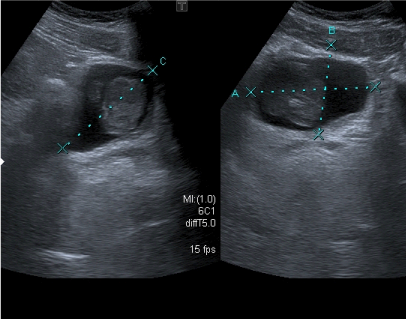

An otherwise healthy 16year old Caucasian male patient was referred with massive painless gross hematuria causing anemia (Hematocrit of 19) that required transfusion with 8 units of blood. He had no history of bleeding disorders, trauma or surgery. Physical examination was essentially negative with rectal examination revealing no masses. Cystoscopy, done elsewhere, was inconclusive due to obscured vision from bleeding. All laboratory tests, including a coagulation profile were normal. Ultrasound showed a 7cm mass occupying the right lateral wall of the bladder with no hydronephrosis (Figure 1). Repeat cystoscopy showed a large pedunculated mass arising from the right anterolateral wall with significant bladder clots. Transurethral resection of all visible tumors was performed, submitting around 37grams of tissue for pathology. Pathology revealed an inflammatory bladder tumor with atypical spindle cells with abundant eosinophilic cytoplasm embedded in a predominantly myxoid stroma , all consistent with IMT; immunohistochemistry showed that tumor was strongly positive to anaplastic lymphoma kinase 1 (ALK1) , Cytokeratin AE1/AE3 and local weak Muscle Specific Actin (MSA) (Figure 2). The differential diagnosis included postoperative spindle cell nodule, rhabdomyosarcoma, leiomyoma and sarcomatous carcinoma. The absence of a history of surgical manipulation, dense eosinophilia, severe atypia and the unique immunohistochemical profile argued against the aforementioned diagnoses. Partial cystectomy and right pelvic node dissection was performed. Intra-operative resection margins were negative. The patients did very well post-operatively and a CT scan of the pelvis at one year follow showed no evidence of recurrent tumor.

Figure 1 Ultrasound shows a mass occupying the right lateral wall of the bladder.